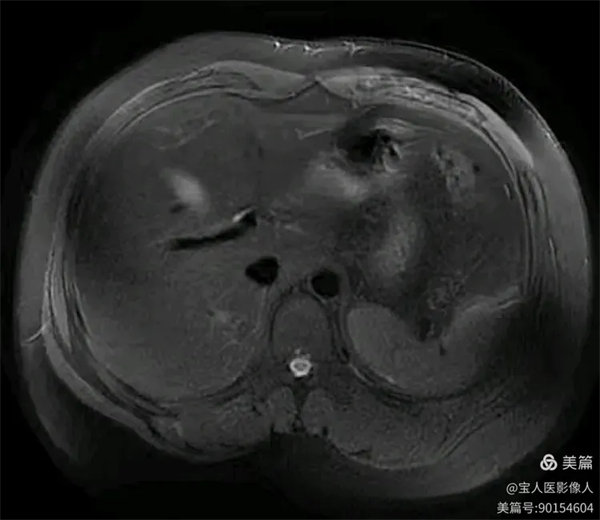

圖2

T2WI冠位,軸位,肝實質信號略增高,而脾臟信號正常。